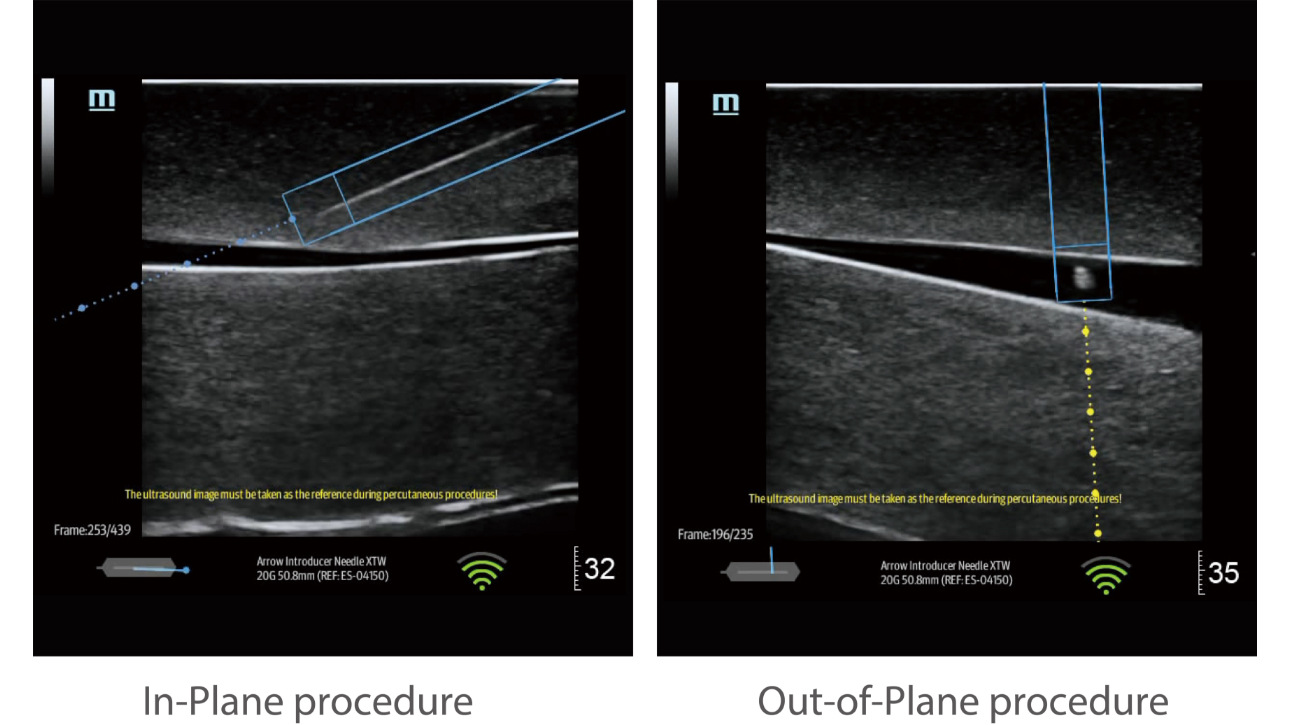

eSpacial Navi??and iNeedle+TM?ensure safe needling solution. Up to 20MHz ultra-high frequency linear transducer can visualize the finest nerves and fibers with extremely high resolution. Seamless monitor with full touch screen and exclusive clean-lock function ensure efficient cleaning and disinfection. The multiple modality design enables the TE5 to easily handle a wide range of medical scenarios.